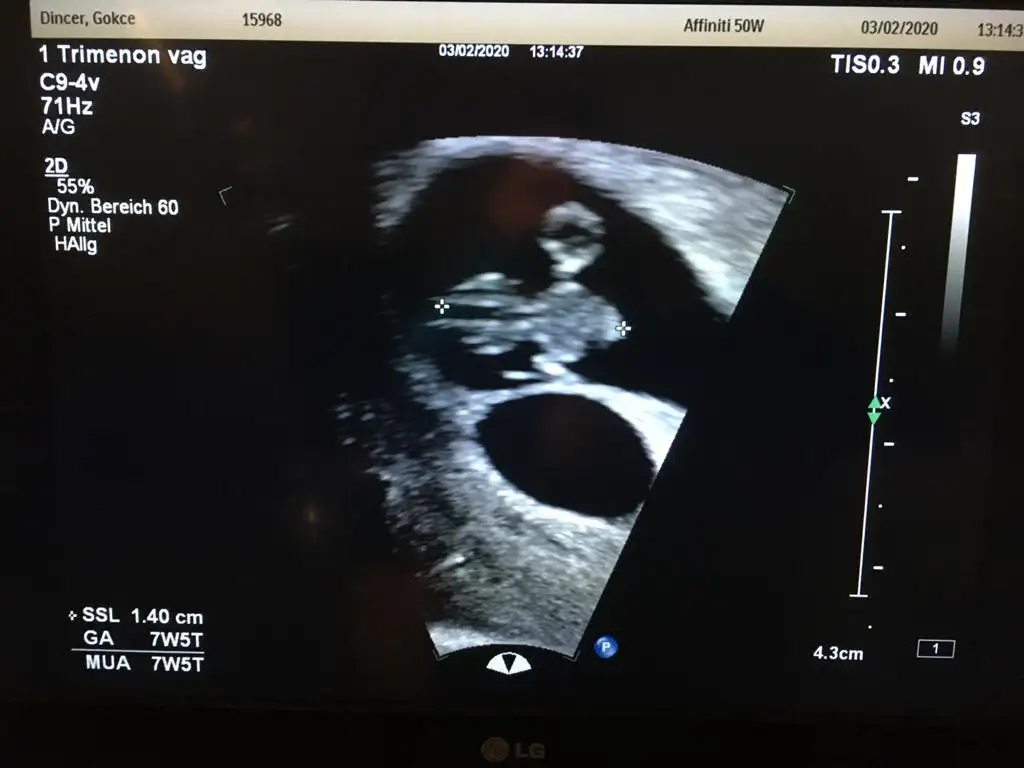

Kızlar çok şükür bugün ilk kez kalp atışı ni duyduk bebegimin. Darısı duymayan kardeslerime inş.

Yalnız benim normal 7+6gozukuyor ama su anki haftası daha 6+3 çok fark yok mu.

Doktor 5.gün olduğu için normal dedi ama

Kızlar benim de bugunkü muayene iyi geçti hamdolsun, bebek oluşmuş. Tek embriyo olmasına rağmen altta bir kese daha görünüyor. Böyle olup sonradan bebeği görünen var mı? Riskli bir durum mudur, ne dersiniz??

Tek embriyo da bölünüp tek yumurta ikizi olabiliyor ama ikinci kesenin içi boş gibi ? Yine de zaman gösterir , sonucta bir tanesini garantiledin ; ikincisi gelirse sürpriz olur 😉